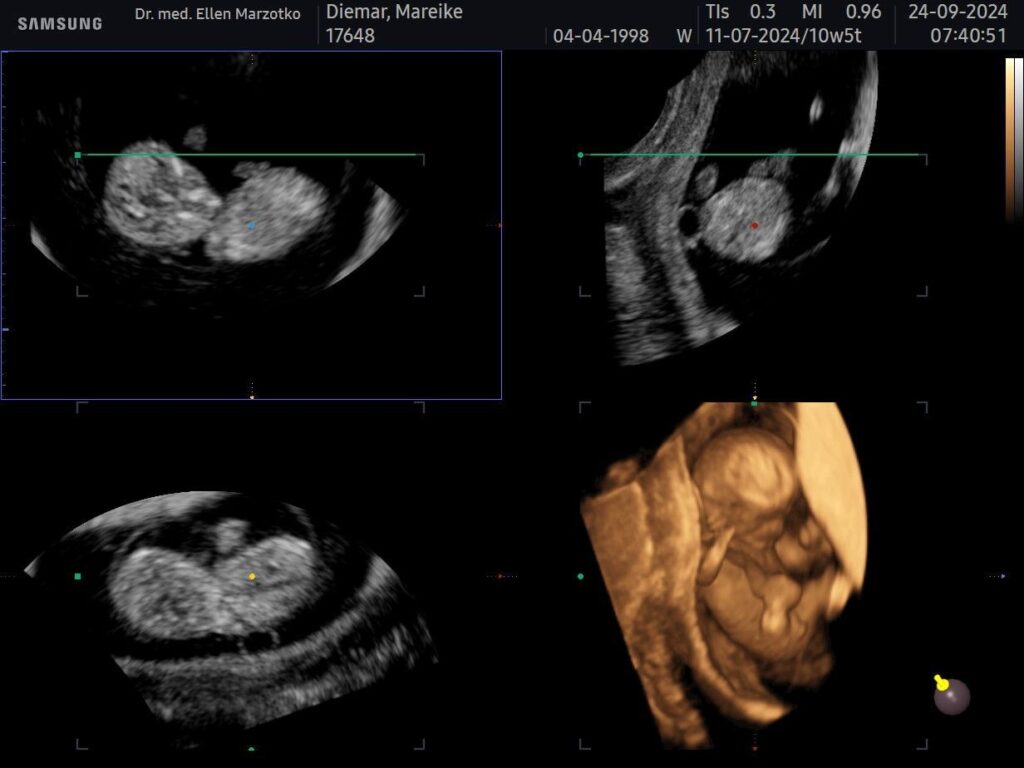

Am 24.09.2024 haben wir dich endlich wieder sehen können. Da warst du gerade mal 4 cm groß und ich in der 11. SSW.